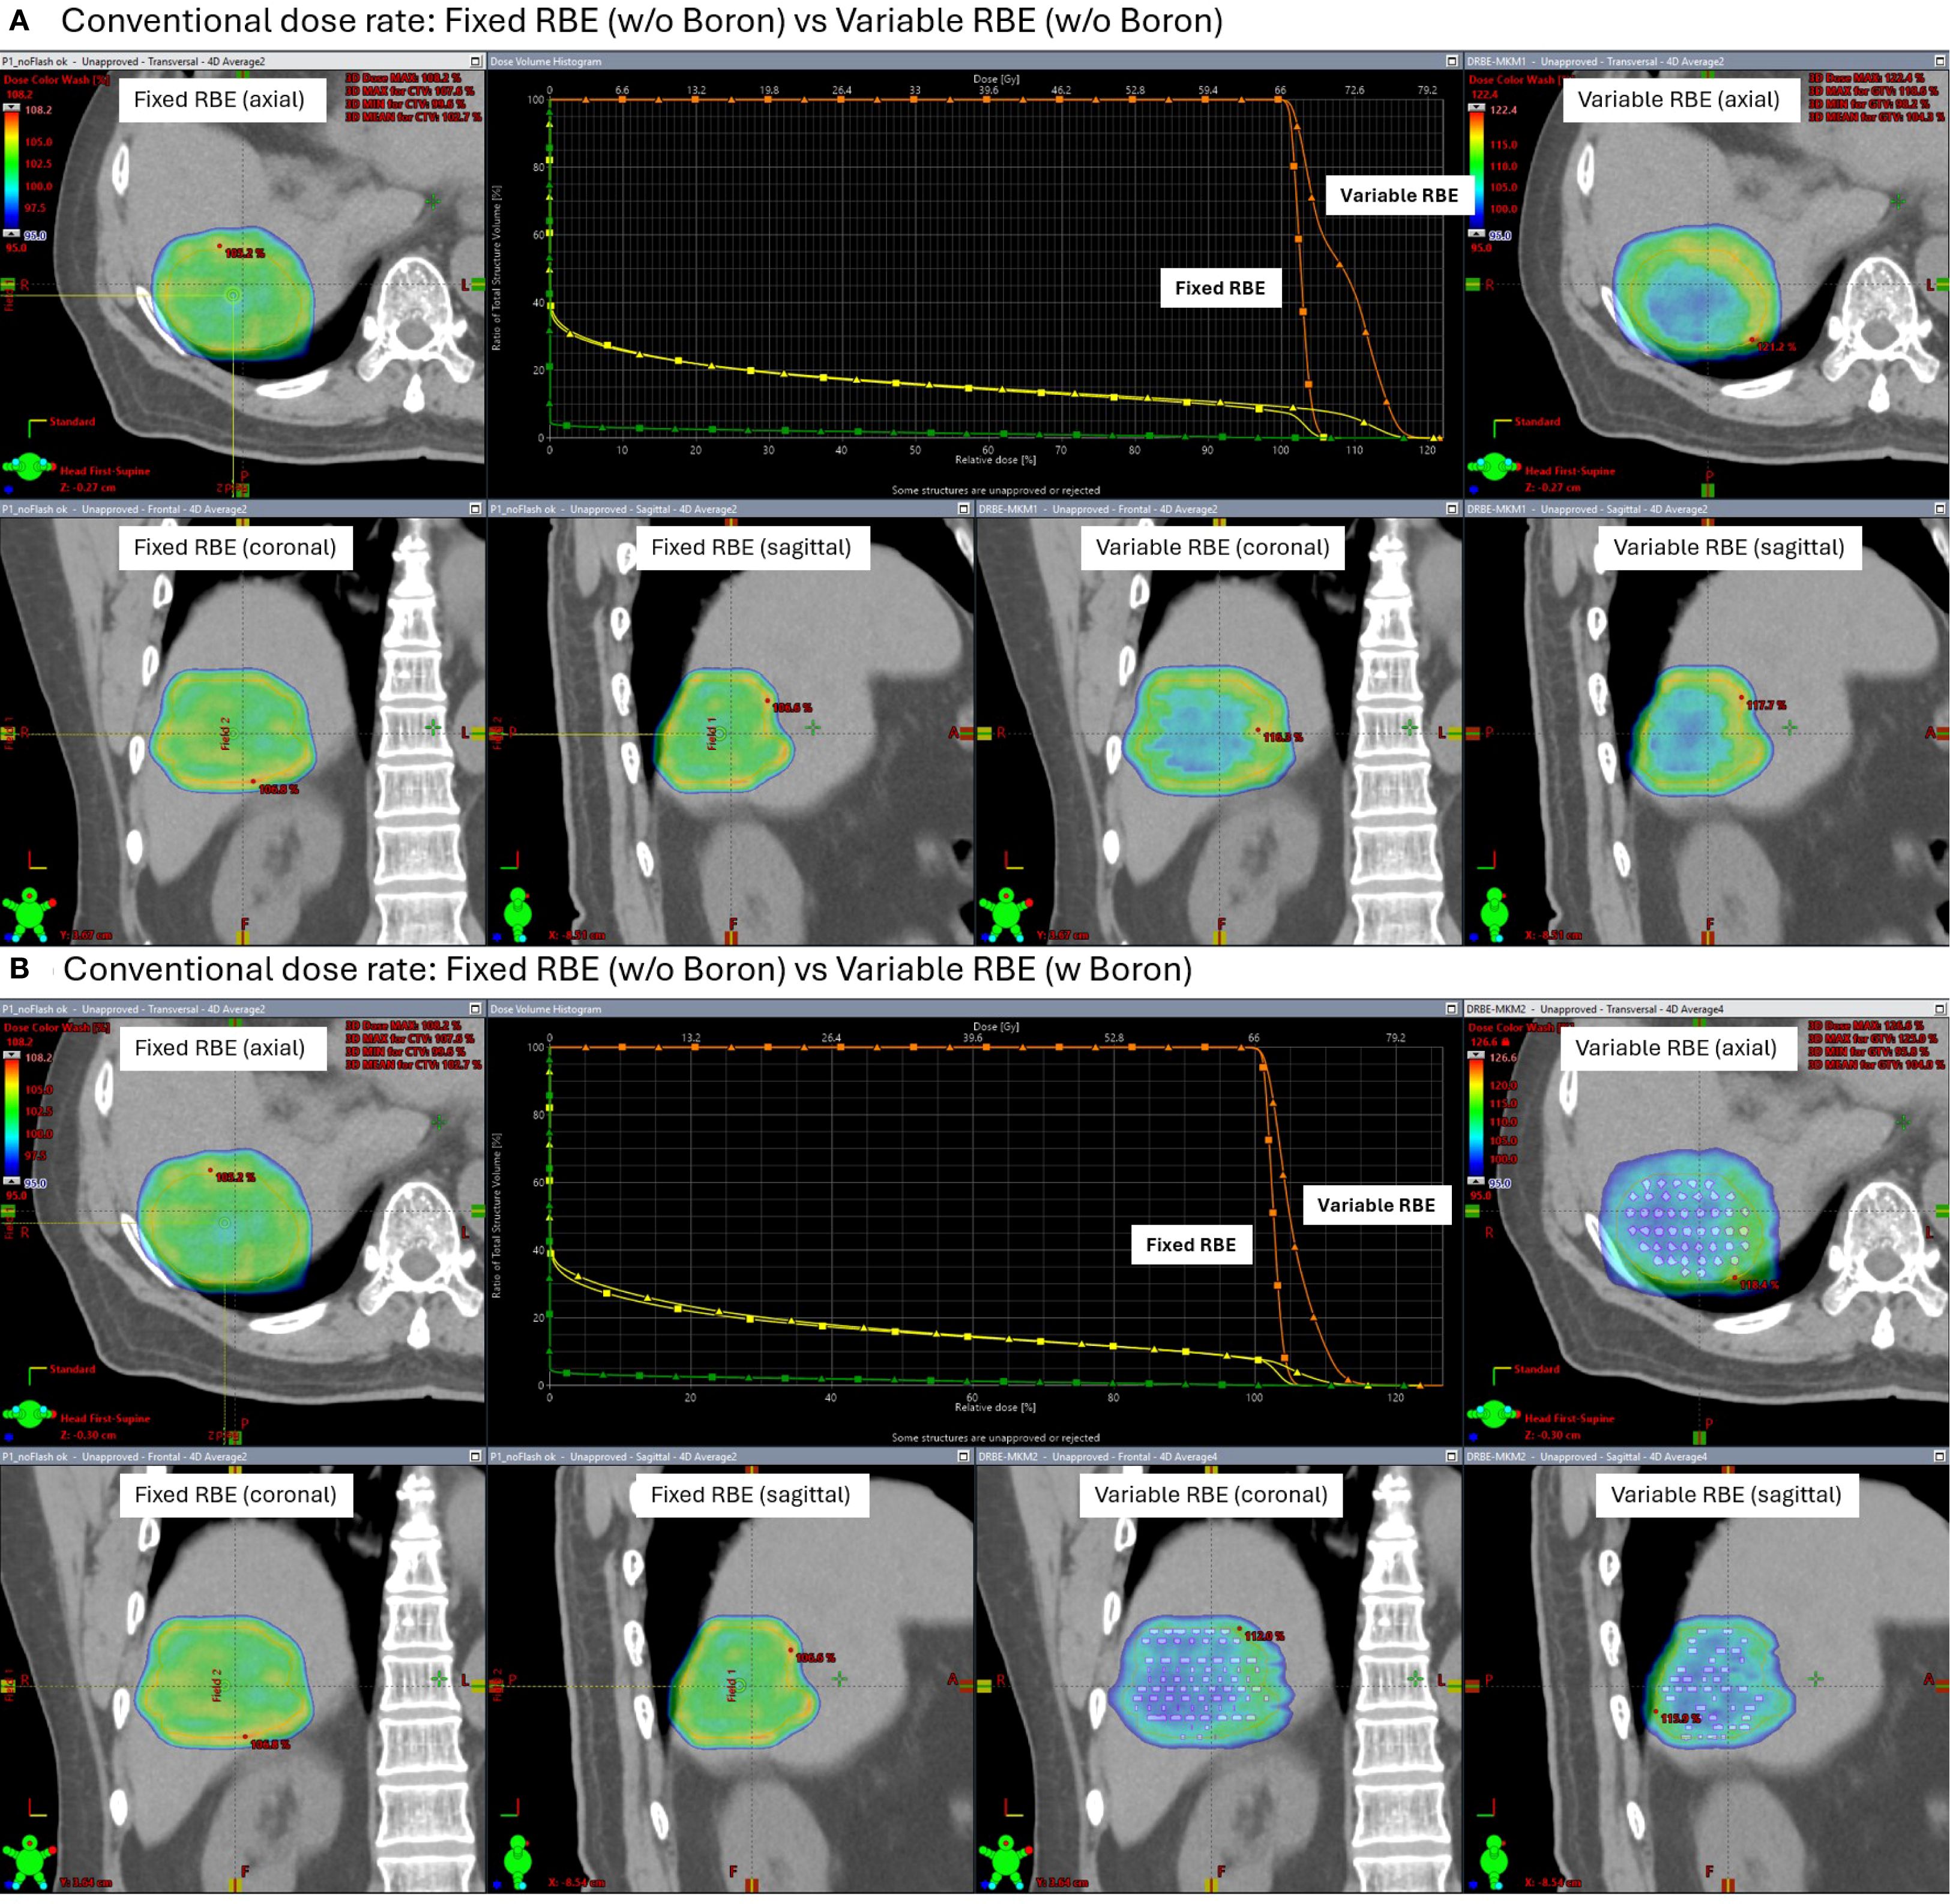

Figures 7 and 8 show the dose distributions and dose volume histogram (DVH) across the CTV under conventional and FLASH dose-rate conditions, respectively. Each figure includes comparisons between fixed and variable RBE dose calculations, with and without the high-density insert. Under conventional dose rates (Figure 7), the variable RBE plan without the insert exhibited dose heterogeneity due to LET variation. When the high-density insert was included, dose uniformity in the CTV improved, indicating that localized changes in stopping power can affect LET-weighted biological dose.

Figure 7

Medical imaging comparison panels showing dose distribution for fixed and variable relative biological effectiveness (RBE) in the context of boron presence. Panel A (top) compares fixed and variable RBE without boron, including axial, coronal, and sagittal views with a dose-response graph. Panel B (bottom) repeats the comparison but with boron, showing similar view orientations and another graph. Brightly colored overlays indicate dose regions within the scans.

Figure 7. Simulated dose distributions and Dose Volume Histogram (DVH) under conventional proton therapy. Comparisons are shown between fixed and variable relative biological effectiveness (RBE) models, both without (A) and with (B) a high-density boron insert (2.34 g/cm³) placed in the CTV.

Under FLASH dose-rate conditions (Figure 8), the difference between fixed and variable RBE distributions was reduced even without the insert suggesting that FLASH delivery may inherently mitigate LET-driven dose variations. When the high-density region was added under FLASH, further improvement in dose homogeneity was observed, reinforcing the idea that both dose rate and local stopping power changes can influence biological dose shaping.